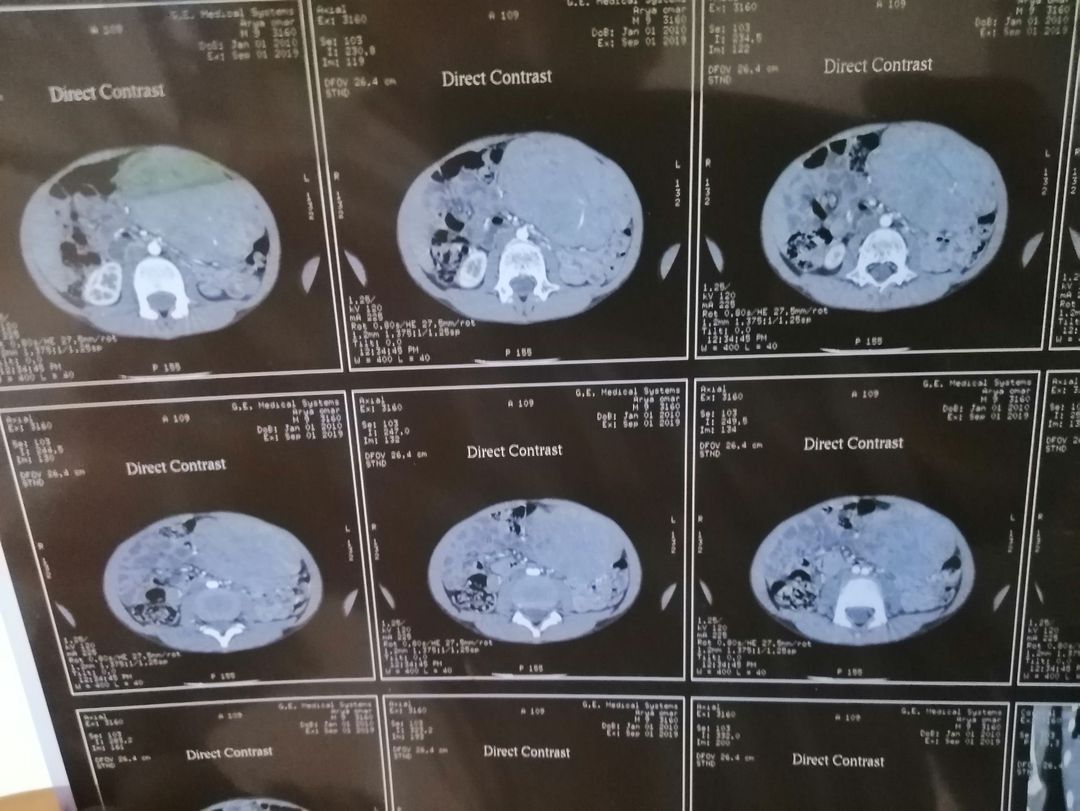

a 9 years old male just anorexia for long time . without any sign and symptoms. palpation exam showed enlarged and rigid left upper quadrant spleen